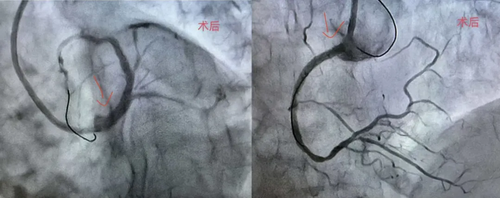

患者因不稳定型心绞痛入院,冠脉造影显示:左主干狭窄约95%,右冠状动脉狭窄约99%。左主干是心脏供血的主要通道,右冠亦为主要血管,双支同时重度狭窄在临床上属高风险病变,意味着患者随时可能因血管急性闭塞引发大面积心肌梗死,猝死风险极高。

手术由心血管病科副主任廖智多主刀。团队先迅速处理近乎闭塞的右冠,稳定患者生命体征;随后集中处理左主干病变。术中,术者凭借丰富经验精准操作导丝通过、球囊扩张及支架植入,全程严密监控患者血压、心率变化。最终支架定位精准,血流恢复通畅,手术圆满成功。

该手术难点在于:双支严重病变且涉及左主干,术中任何细微波动都可能导致血流动力学崩溃;高龄患者代偿能力差,对手术创伤及缺血时间的耐受性较低,对术者技术及团队应急能力要求极高。术后患者生命体征平稳,胸痛症状明显缓解,已转入病房康复。